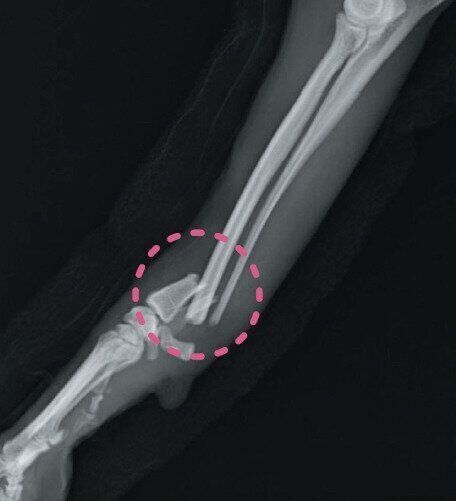

撓尺骨骨折のレントゲン写真

参考・写真/「いぬのきもち」2025年12月号『サインを見逃さないで!冬に気をつけたい犬の痛い!病気』より 枝村一弥先生提供

骨折や脱臼は季節に関係なく起きますが、冬ならではの理由で発症するものもあります。発症すると多くの場合で激しい痛みを伴います。積雪や道の凍結のほか、来客が増える年末年始など、次のようなシチュエーションに注意してください。